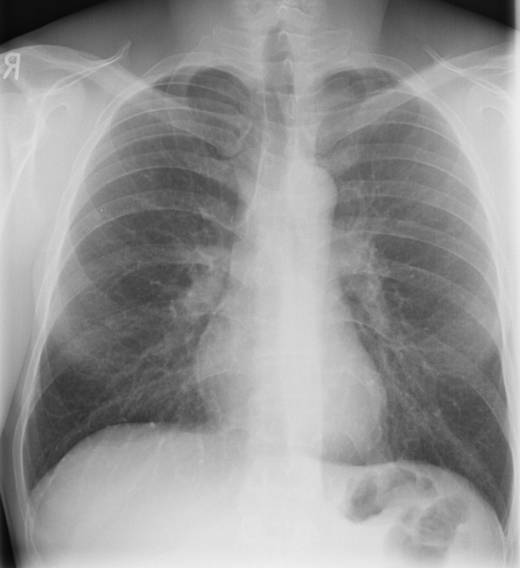

1a: Normal chest X-ray 1b: Chest HRCT examination